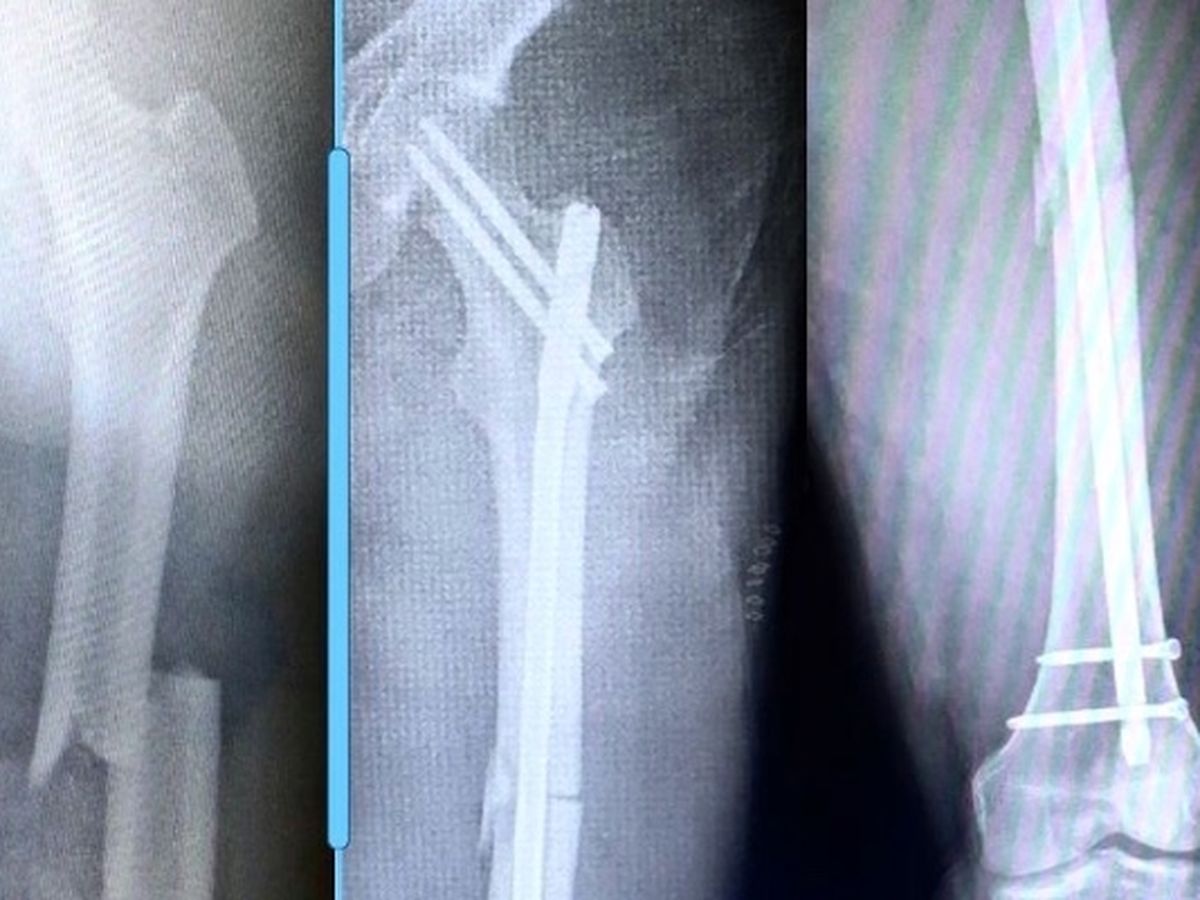

Back in the beginning of August, Cas broke his femur. The following morning, they performed emergency surgery to repair the break by inserting a rod through the bone and a handful of screws to hold to whole mess together.